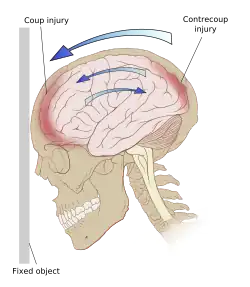

Even in the absence of an impact, significant acceleration or deceleration of the head can cause TBI; however in most cases, a combination of impact and acceleration is probably to blame.[37] Forces involving the head striking or being struck by something, termed contact or impact loading, are the cause of most focal injuries, and movement of the brain within the skull, termed noncontact or inertial loading, usually causes diffuse injuries.[20] The violent shaking of an infant that causes shaken baby syndrome commonly manifests as diffuse injury.[66] In impact loading, the force sends shock waves through the skull and brain, resulting in tissue damage.[37] Shock waves caused by penetrating injuries can also destroy tissue along the path of a projectile, compounding the damage caused by the missile itself.[23]

Damage may occur directly under the site of impact, or it may occur on the side opposite the impact (coup and contrecoup injury, respectively).[65] When a moving object impacts the stationary head, coup injuries are typical,[67] while contrecoup injuries are usually produced when the moving head strikes a stationary object.[68]